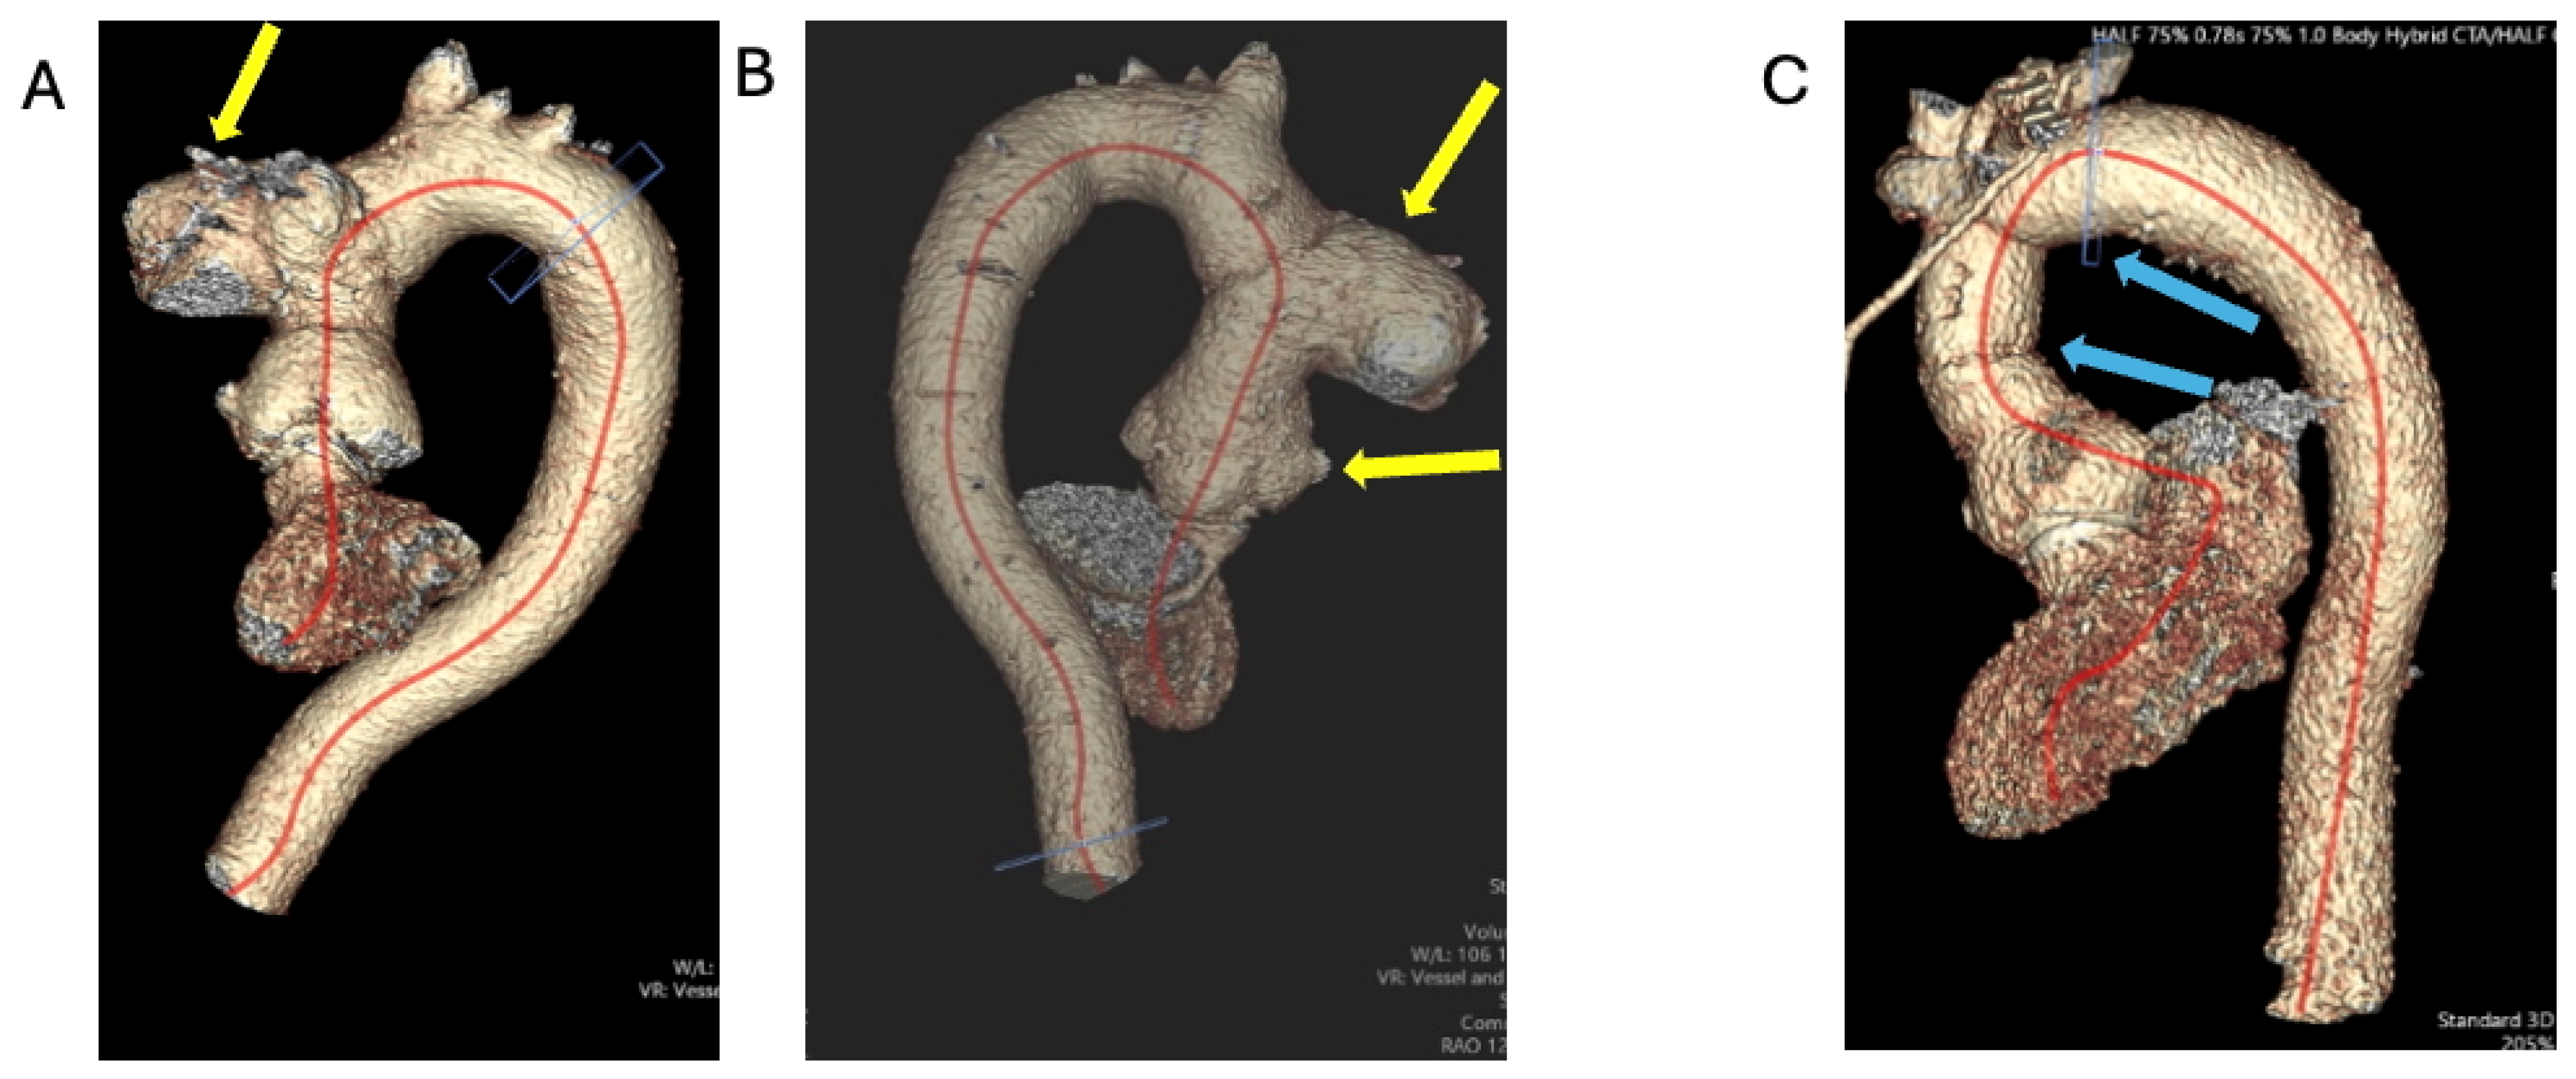

1.1.2. Case 2